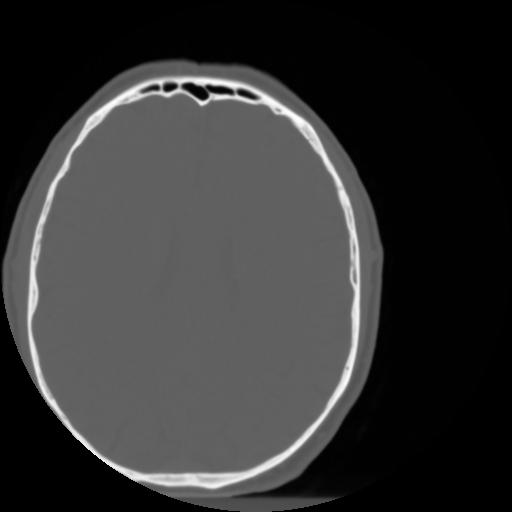

3 CEREBRO,,Axial,3.0,CEREBRO,,